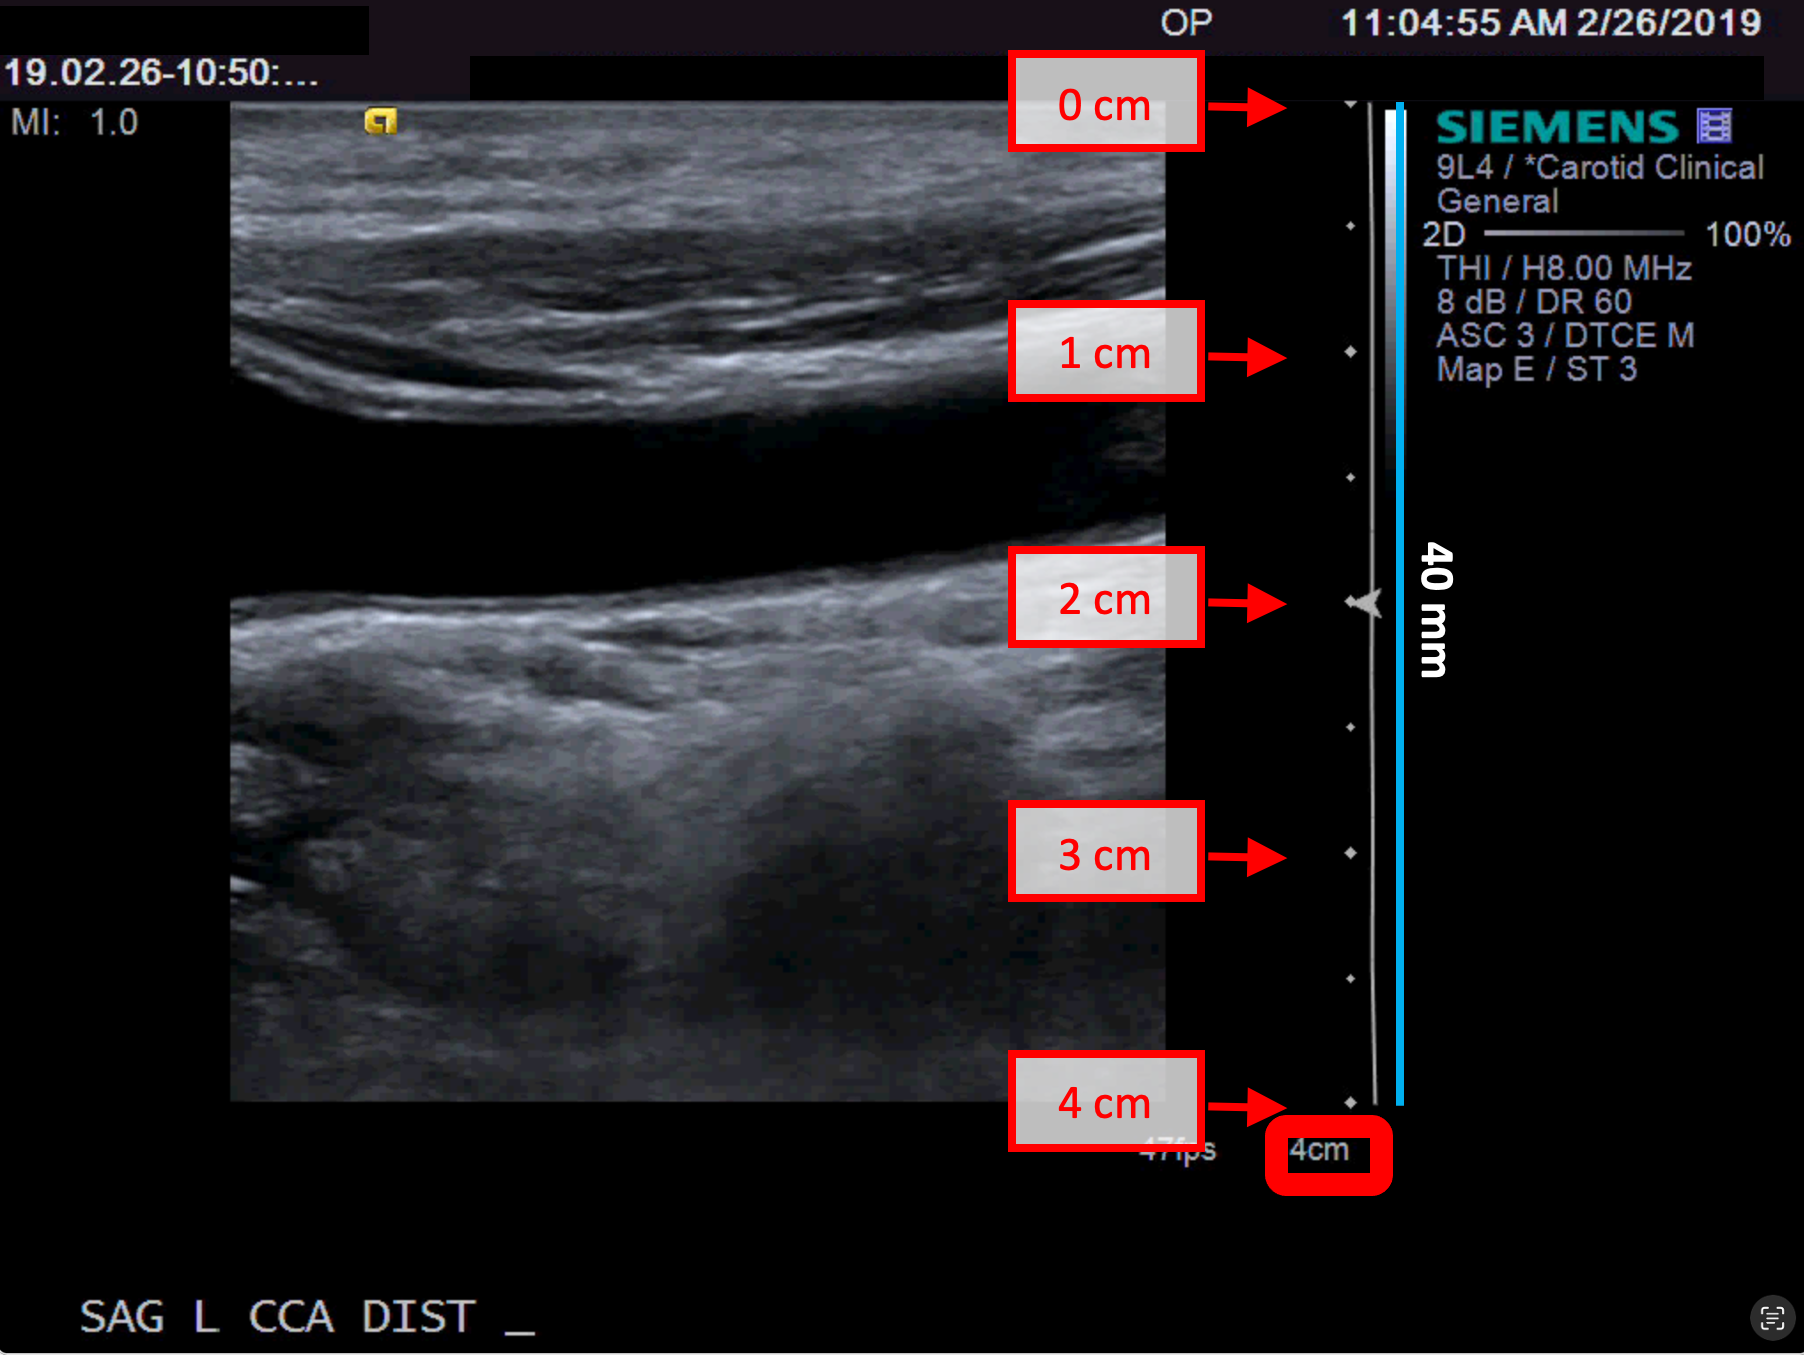

• Individuare, nell'immagine ecografica, una distanza nota (30 mm. nell'esempio in figura).

Esempi di calibrazione in modalità B

Le immagini seguenti mostrano esempi di calibrazione dell'immagine in modalità B. Gli elementi grafici in rosso indicano dove è possibile trovare informazioni sulla profondità dell'immagine nell'immagine ecografica.